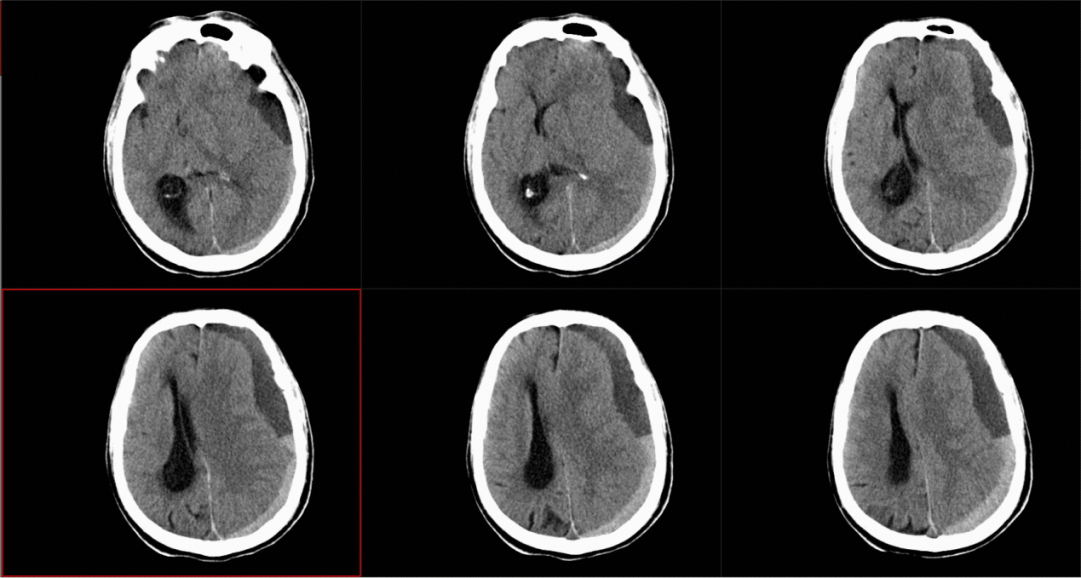

急诊CT影像,见左侧硬膜下混杂慢性硬膜下血肿,中线受压右移。

慢性硬膜下血肿就是发生在硬脑膜和蛛网膜之间的血肿,通常是头部受到轻微外伤后,少量出血逐渐积累形成的“血包”,这个形成过程可能持续数周甚至数月。